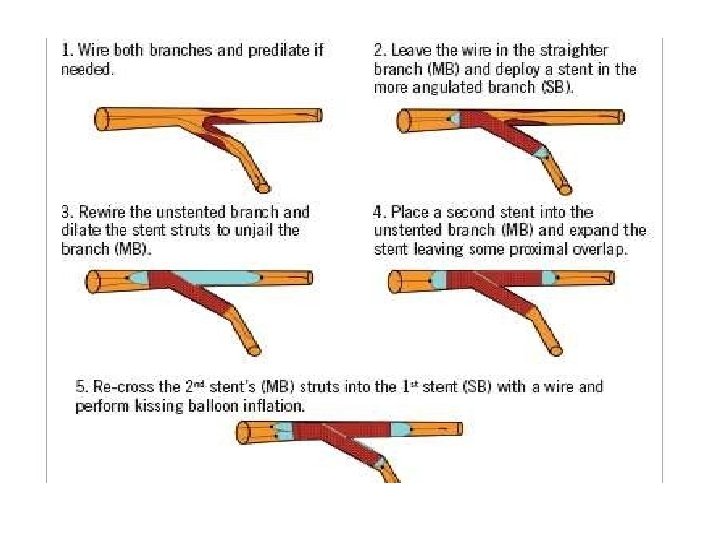

Culotte technique

� It provides near-perfect coverageof the carina &SBostium atthe expense of an excessof metal covering in proximal. MB. � Bestimmediate angiographic result &theoretically itmayguarantee a more homogeneous distribution of struts &drug. � Canbeused in all bifurcation lesions irrespective of bifurcationangle. � Open-cell stents arepreferred when the SBdiameter is >3 mm. � Disadvantages – � Complexity in the rewiring of both branches through the stentstruts, � Not advisable if both branches aredissected afterpredilatation.